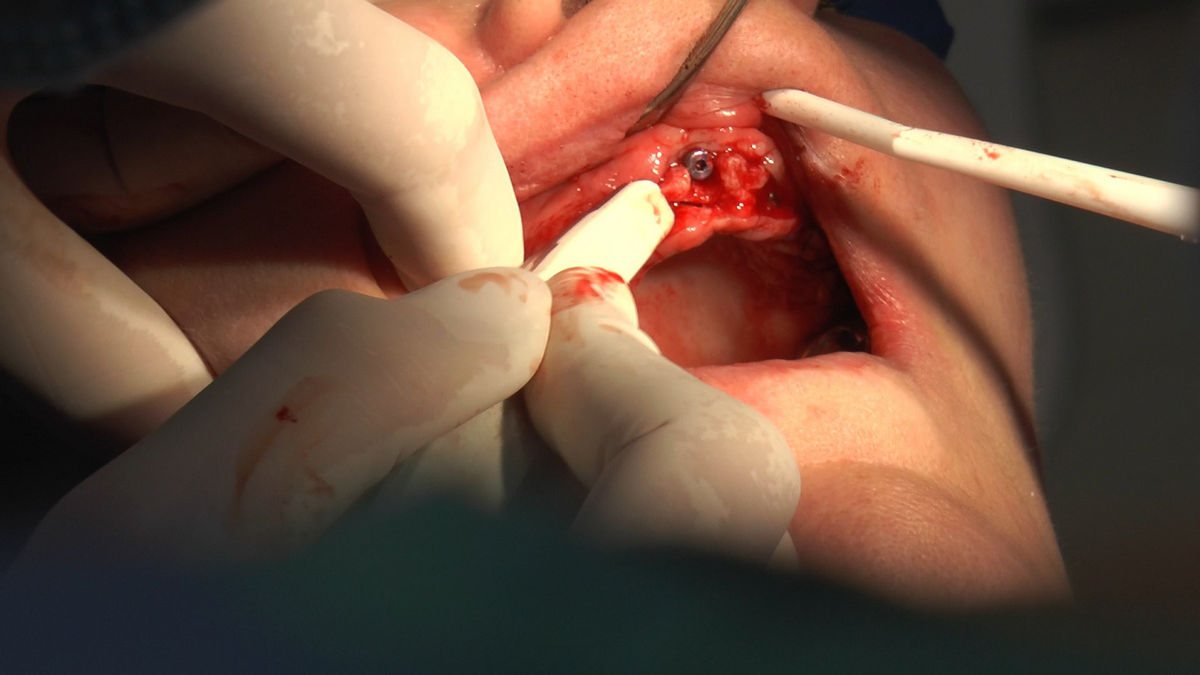

Practiculum Implantologii – Sezon V/B, sesja 8, część 4